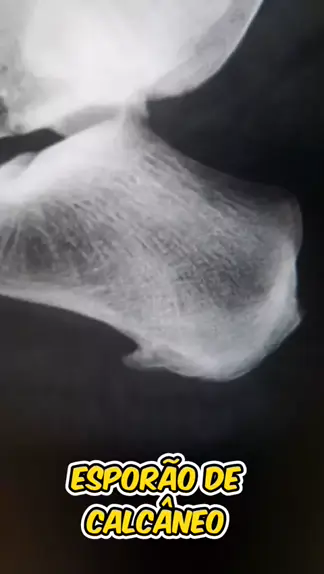

Esporão de calcâneo. Saiba oque isso é. #saude #vida #radiologia #medicina